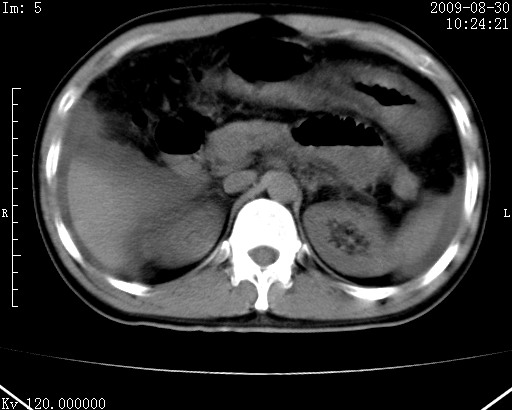

患者唐某,男31岁,已婚,本地务农。

自述入院前两天一次进食较多冷饮之后,出现阵发性上腹部疼痛,次日加剧伴恶心、呕吐,呕吐后症状稍减轻。食欲差。大便每天1-2次,量少,暗红色水样。小便赤。无畏寒、发热、咳嗽等呼吸道症状。无高血压及胃病史。

检查:体温、血压及脉搏正常.皮肤无黄染,浅表无淋巴结肿大。左腹肌紧张,左上腹有压痛,无反跳痛,可触及包块。

生化:钾、钠、氯、钙、ph正常,总胆红素和直接胆红素稍高,空腹血糖稍高。

尿淀粉酶:1256 u/l(正常60-401)。

血常规:wbc 22.4x109/l gr88% ly9.6%其余基本正常。

胃镜:急性胃炎。立位腹平片:未见异常。

下面是ct平扫,降结肠内是对比剂。

术前影像诊断:上段空肠急性缺血性坏死并腹水。建议手术治疗。

术中见上段空肠约70cm长范围坏死,从屈氏韧带远端约10cm处开始。坏死肠管肿胀变形变色,管壁明显环形增厚,部分聚成大肿块,无扭转和套叠。肠系膜上动脉分支内广泛泥沙状血栓。肠切除。

临床诊断:肠系膜上动脉梗塞并急性肠坏死。

开始时我们科也有人认为是套叠,最后统一意见,不考虑肠套。我们看到的“靶征”,“晕圈征”,“双圈征”实际上只是单根肠管的横断面。坏死肿胀后肠壁各层的密度不一样。

左侧腹小肠腔管壁明显增厚,部分内示靶征,走行异常,部分肠系膜绳样改变,肝包膜下及肠间较多液体密度,然梗阻近端肠腔积气不明显。

考虑;肠扭曲伴肠坏死。